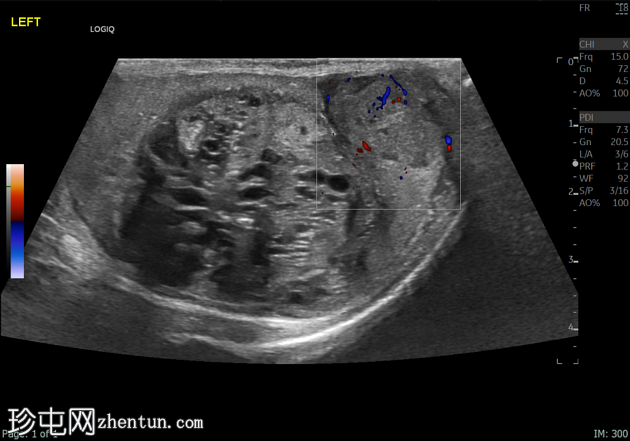

左侧睾丸肿大,体积约56 mL,可见弥漫性微结石,以及三个内部等回声病灶,伴囊性变、微钙化和明显血流信号,最大病灶大小约4.8 x 3.2 cm。

未见腹主动脉旁或髂淋巴结肿大。